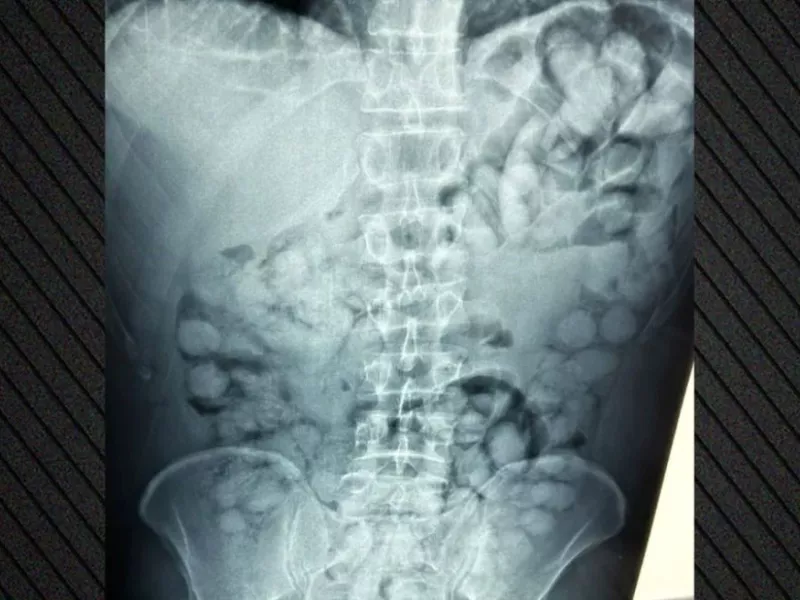

Ένας άνδρας από τη Βραζιλία συνελήφθη το πρωί της Δευτέρας στο αεροδρόμιο «Ελευθέριος Βενιζέλος», καθώς κατηγορείται ότι μετέφερε μεγάλη ποσότητα κοκαΐνης με τη μέθοδο της κατάποσης.

Όπως ανακοίνωσε η ΕΛ.ΑΣ., ο συλληφθείς είχε φτάσει στην Αθήνα μέσω Παρισιού και κατά τον έλεγχο διαπιστώθηκε ότι είχε καταπιεί περίπου 100 μικροδέματα της ναρκωτικής ουσίας.